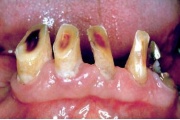

Lutipudelikaariese kahjustused

Lutipudelikaaries